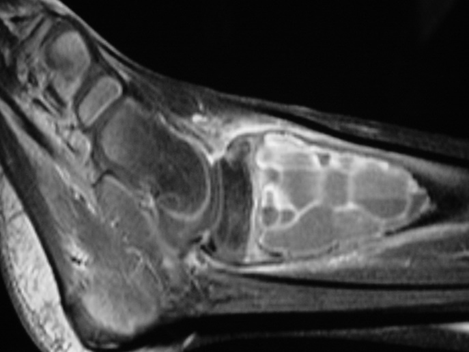

MRI

- Geographic well circumscribed

- High signal on T2 weighted MRI images

- Fluid/Fluid level (T2) are highly characteristic

Fig 2 a-e. MRI of an ABC of Distal Tibia: Fig 2 a-c: geographic cystic expansile lesion with fluid-fluid levels. The fluid-fluid levels are caused by bleeding into the cavities. The blood collects and the degredation products settle to the gravity dependent areas of the cavities. This shows up as fluid-fluid levels on the MRI. Fig 2 d,e: This is a gadolinium enhanced MRI of the ABC of the distal tibia. There is peripheral and septal enhancement indication cyst formation. The contrast outlines the cystic cavities but does not enter into the center